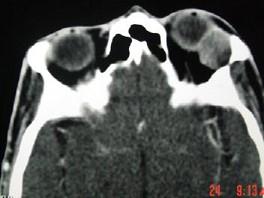

问题 女,36岁,左眼眶外上部可触及一无痛性包块有2年,眼球向内下方突出,CT检查如图,最可能诊断为()

选项 A.泪腺良性混合瘤 B.泪腺恶性上皮性肿瘤 C.炎性假瘤 D.淋巴瘤 E.淋巴瘤样增生

答案 A